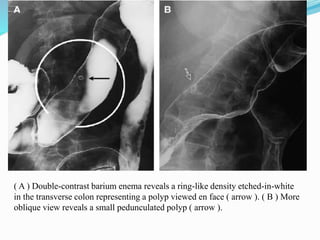

This document discusses colorectal polyps. It defines polyps and describes their types, including neoplastic and non-neoplastic polyps. It discusses adenomatous polyps in depth, noting their malignant potential increases with size over 1cm and villous architecture. Radiological diagnostic methods for polyps including single and double contrast barium enema and CT colonography are explained. The document provides an overview of polyp pathogenesis and genetic syndromes like FAP that increase cancer risk.